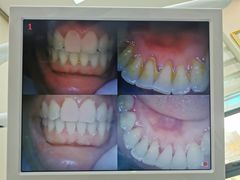

• 新达口腔(华东理工大学店)

• -新达口腔(华东理工大学店)

yuanioo | 19-12-10

huige5245016 | 19-12-02

狮子失去记忆 | 19-11-29

Ping嚴 | 19-11-19

wljenny | 19-11-18